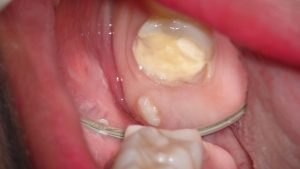

口の中の状態。

頭の一部のみが歯肉から見えていえるのが親知らずです。